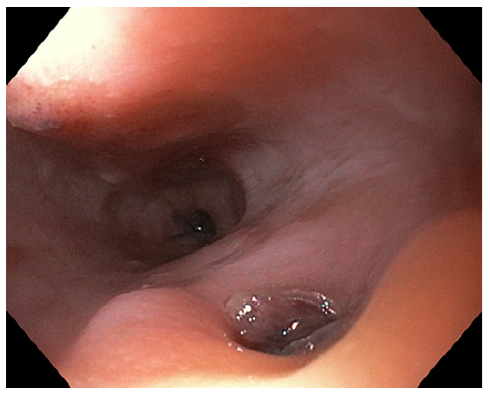

On the eighth day of hospitalization, the patient was readmitted to the intensive care unit in hemorrhagic shock due to new-onset hematemesis. He was intubated and treated with aggressive resuscitation and transfusion of red blood cells. EGD revealed an esophageal 10-mm non-ulcerated mucosal depression with a visible vessel at 20 cm from the incisors (shown in Fig. 1), closed with 3 hemoclips. Thoracic CT angiography showed a brachiocephalic trunk aneurysm with aortoesophageal fistulization (shown in Fig. 2). The vascular surgery department at our hospital and the cardiothoracic surgery department at a tertiary center were consulted, but the patient was deemed unsuitable for endovascular or surgical treatment given the anatomical characteristics of the fistula and his general condition. He subsequently recovered and was able to be discharged home. About 2 months later, the patient was admitted to the emergency room in cardiorespiratory arrest following an episode of hematemesis at home.

EGD plays an important role in the evaluation of upper GI bleeding; however, its sensitivity for AEF diagnosis is low. The diagnosis can easily go unnoticed in endoscopy if there is no active bleeding and because the typical endoscopic findings, such as submucosal tumor-like protrusion or pulsating arterial bleeding, are rarely found [3, 4, 10].